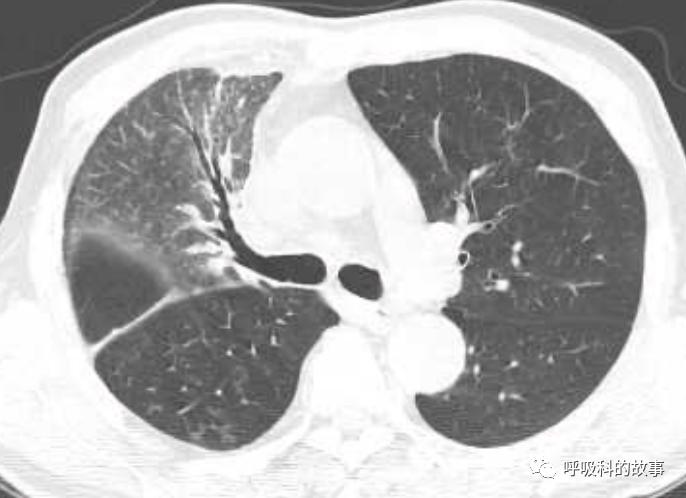

当时我们也曾经考虑给病人做淋巴结活检,但再次遭到患者的拒绝,由于患者体温正常,症状好转,我们也没有坚持。经过了两个多月的伏立康唑治疗,肺部影像基本吸收。

纵隔淋巴结也明显缩小了